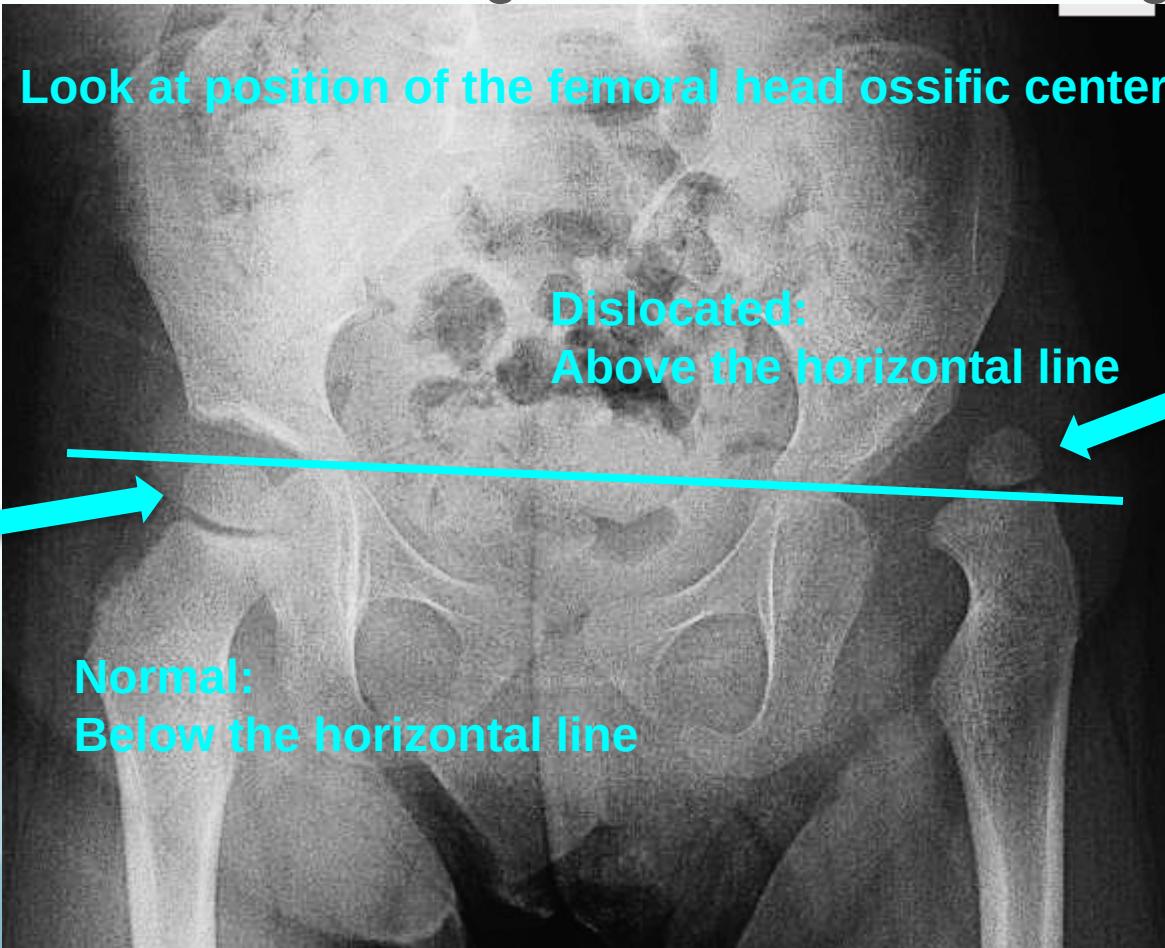

After 6 months:

- Clearly shows dislocation

- Size of femoral head ossific center

- Horizontal line through the tri-radiate cartilage

Position Assessment:

- Dislocated: Above the horizontal line

- Normal: Below the horizontal line